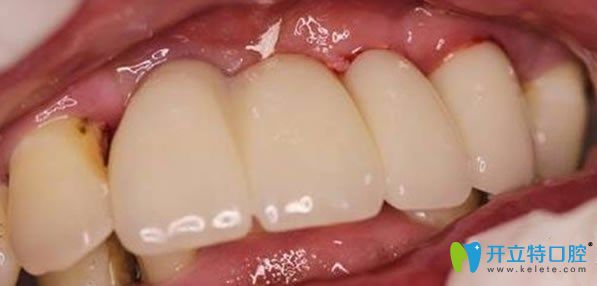

無錫佳士潔口腔多顆牙缺失微創(chuàng)無痛種植牙術(shù)后效果圖:

種植牙手術(shù)后需要5個月的恢復(fù)期,種植體和牙槽骨緊密結(jié)合后,裝上牙冠,即刻承重??吹竭@整齊的牙齒,劉媽心里美滋滋的。無錫佳士潔口腔李永平院長,德國種植牙技術(shù)增強了牙齒的咀嚼功能,吃嘛嘛香,劉媽一直夸贊種植牙是兒子送給她的禮物。